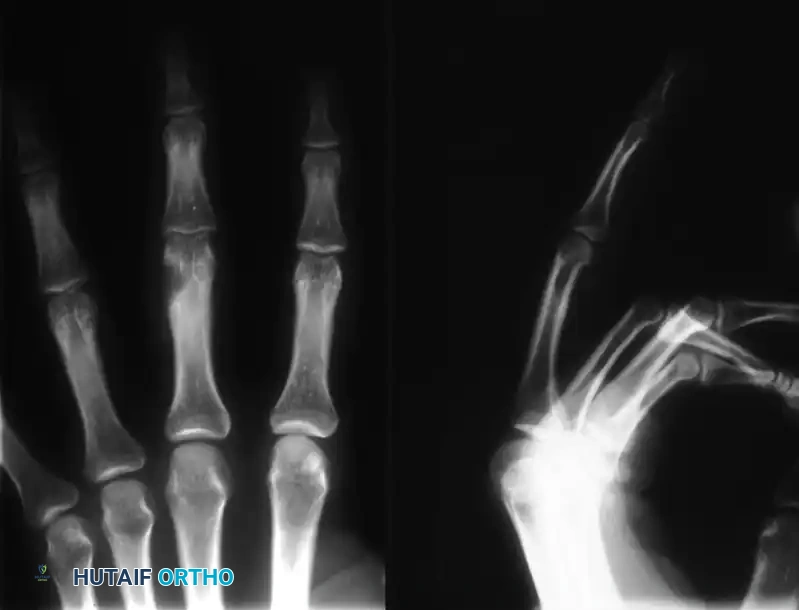

Preoperative radiograph demonstrating an eccentric, expansile enchondroma of the proximal phalanx.

The most frequent anatomical location for an enchondroma is the proximal metaphysis of the proximal phalanx. In this region, the tumor characteristically presents as an eccentric and expansile lytic lesion. Because the hand possesses a thin cortical shell and minimal overlying soft tissue, the loculated medullary tumor often expands the bony cortex, leading to visible, asymmetrical enlargement of the affected finger.

Clinical Pearl: Pathological fracture is the most common presenting complication of a hand enchondroma. The expansile nature of the tumor thins the cortex, creating a significant biomechanical stress riser. Routine torsional forces generated during simple grip or pinch can precipitate an acute fracture through the weakened metaphyseal bone.

Diagnosis is primarily established through a combination of physical examination and orthogonal radiography. Radiographs typically reveal a well-circumscribed, radiolucent, expansile lesion with central calcifications (the classic "rings and arcs" or "popcorn" calcification pattern of chondroid matrix).